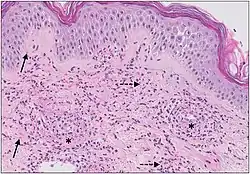

Micrograph of cutaneous small-vessel vasculitis. The section shows all features of leucocytoclastic vasculitis. A mixed inflammatory cell population surrounds the postcapillary venules of the superficial dermis. The infiltrate consists of neutrophils with nuclear dust (dashed arrows) and shows high affinity for the vessels. Features of vascular injury are shown, including fibrinoid necrosis (asterisks) and erythrocyte extravasation (solid arrows).[11]

The small vessels in the skin affected are located in the superficial dermis and include arterioles (small arteries carrying blood to capillaries), capillaries, and venules (small veins receiving blood from capillaries).[5] In general, immune complexes deposit in vessel walls leading to activation of the complement system. C3a and C5a, proteins produced from the complement system, attract neutrophils to the vessels.[9] Once activated, neutrophils then release preformed substances, including enzymes, causing damage to vessel tissue.[9] Evidence of this process can be seen with a sample of removed skin tissue, or biopsy, viewed under a microscope. Neutrophils are seen surrounding blood vessels and their debris within vessel walls, causing fibrinoid necrosis. This finding on histological examination is termed "leukocytoclastic vasculitis".[5]